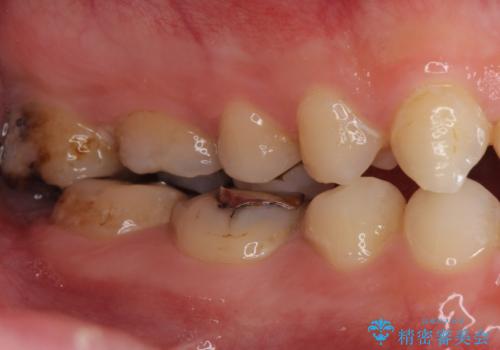

矯正を途中でやめてしまったとのことで、歯に矯正の接着材が残っており着色も顕著でした。

奥歯の咬合面にはレジンが盛られた状態でした。

見た目と咬み合わせを改善するため、セラミッククラウンによる治療を行いました。